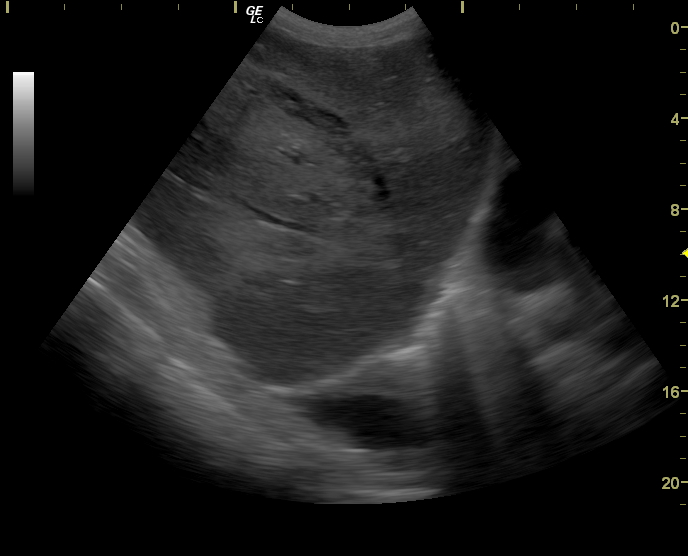

Добавлю еще пару случаев

#2

#3

Краевой разрыв с гемоперитонеумом (вне поля сканирования)